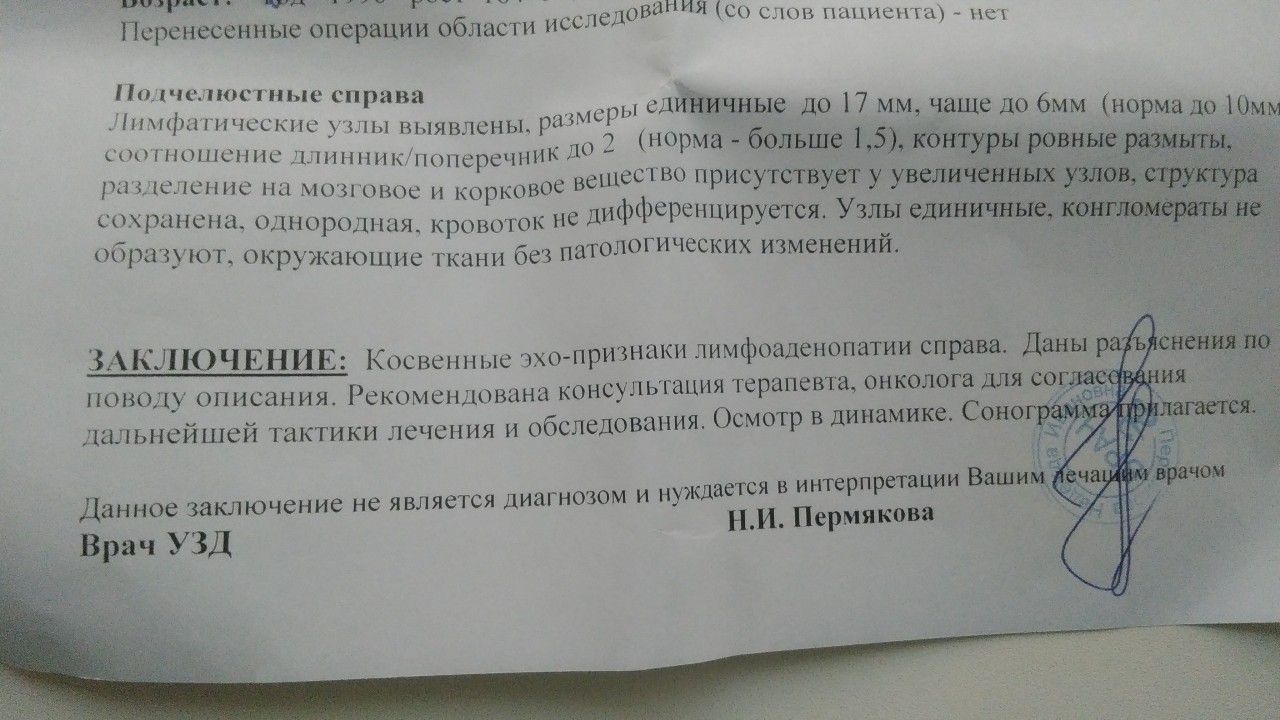

УЗИ лимфоузлов при лимфоме Ходжкина

Раздел: Образы вокруг